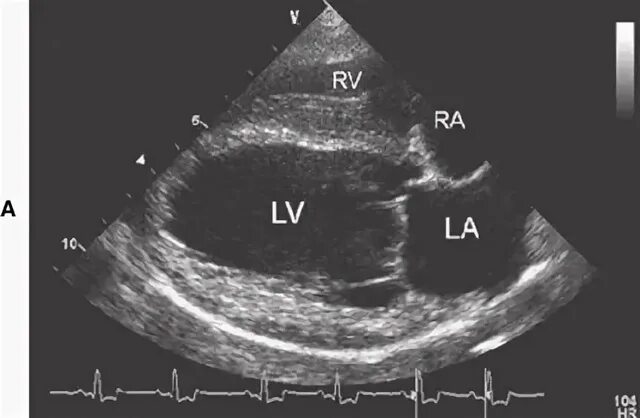

Эхокг 4х камерная позиция. эхокардиография собак. эхокардиография сердца. узи сердца проекции.

Эхокг анатомия. эхокг анатомия сердца. проекции эхокг. узи сердца проекции.

Эхокг норма снимок. узи сердца (эхокардиография). узи сердца норма снимок. эхокг норма рисунок.